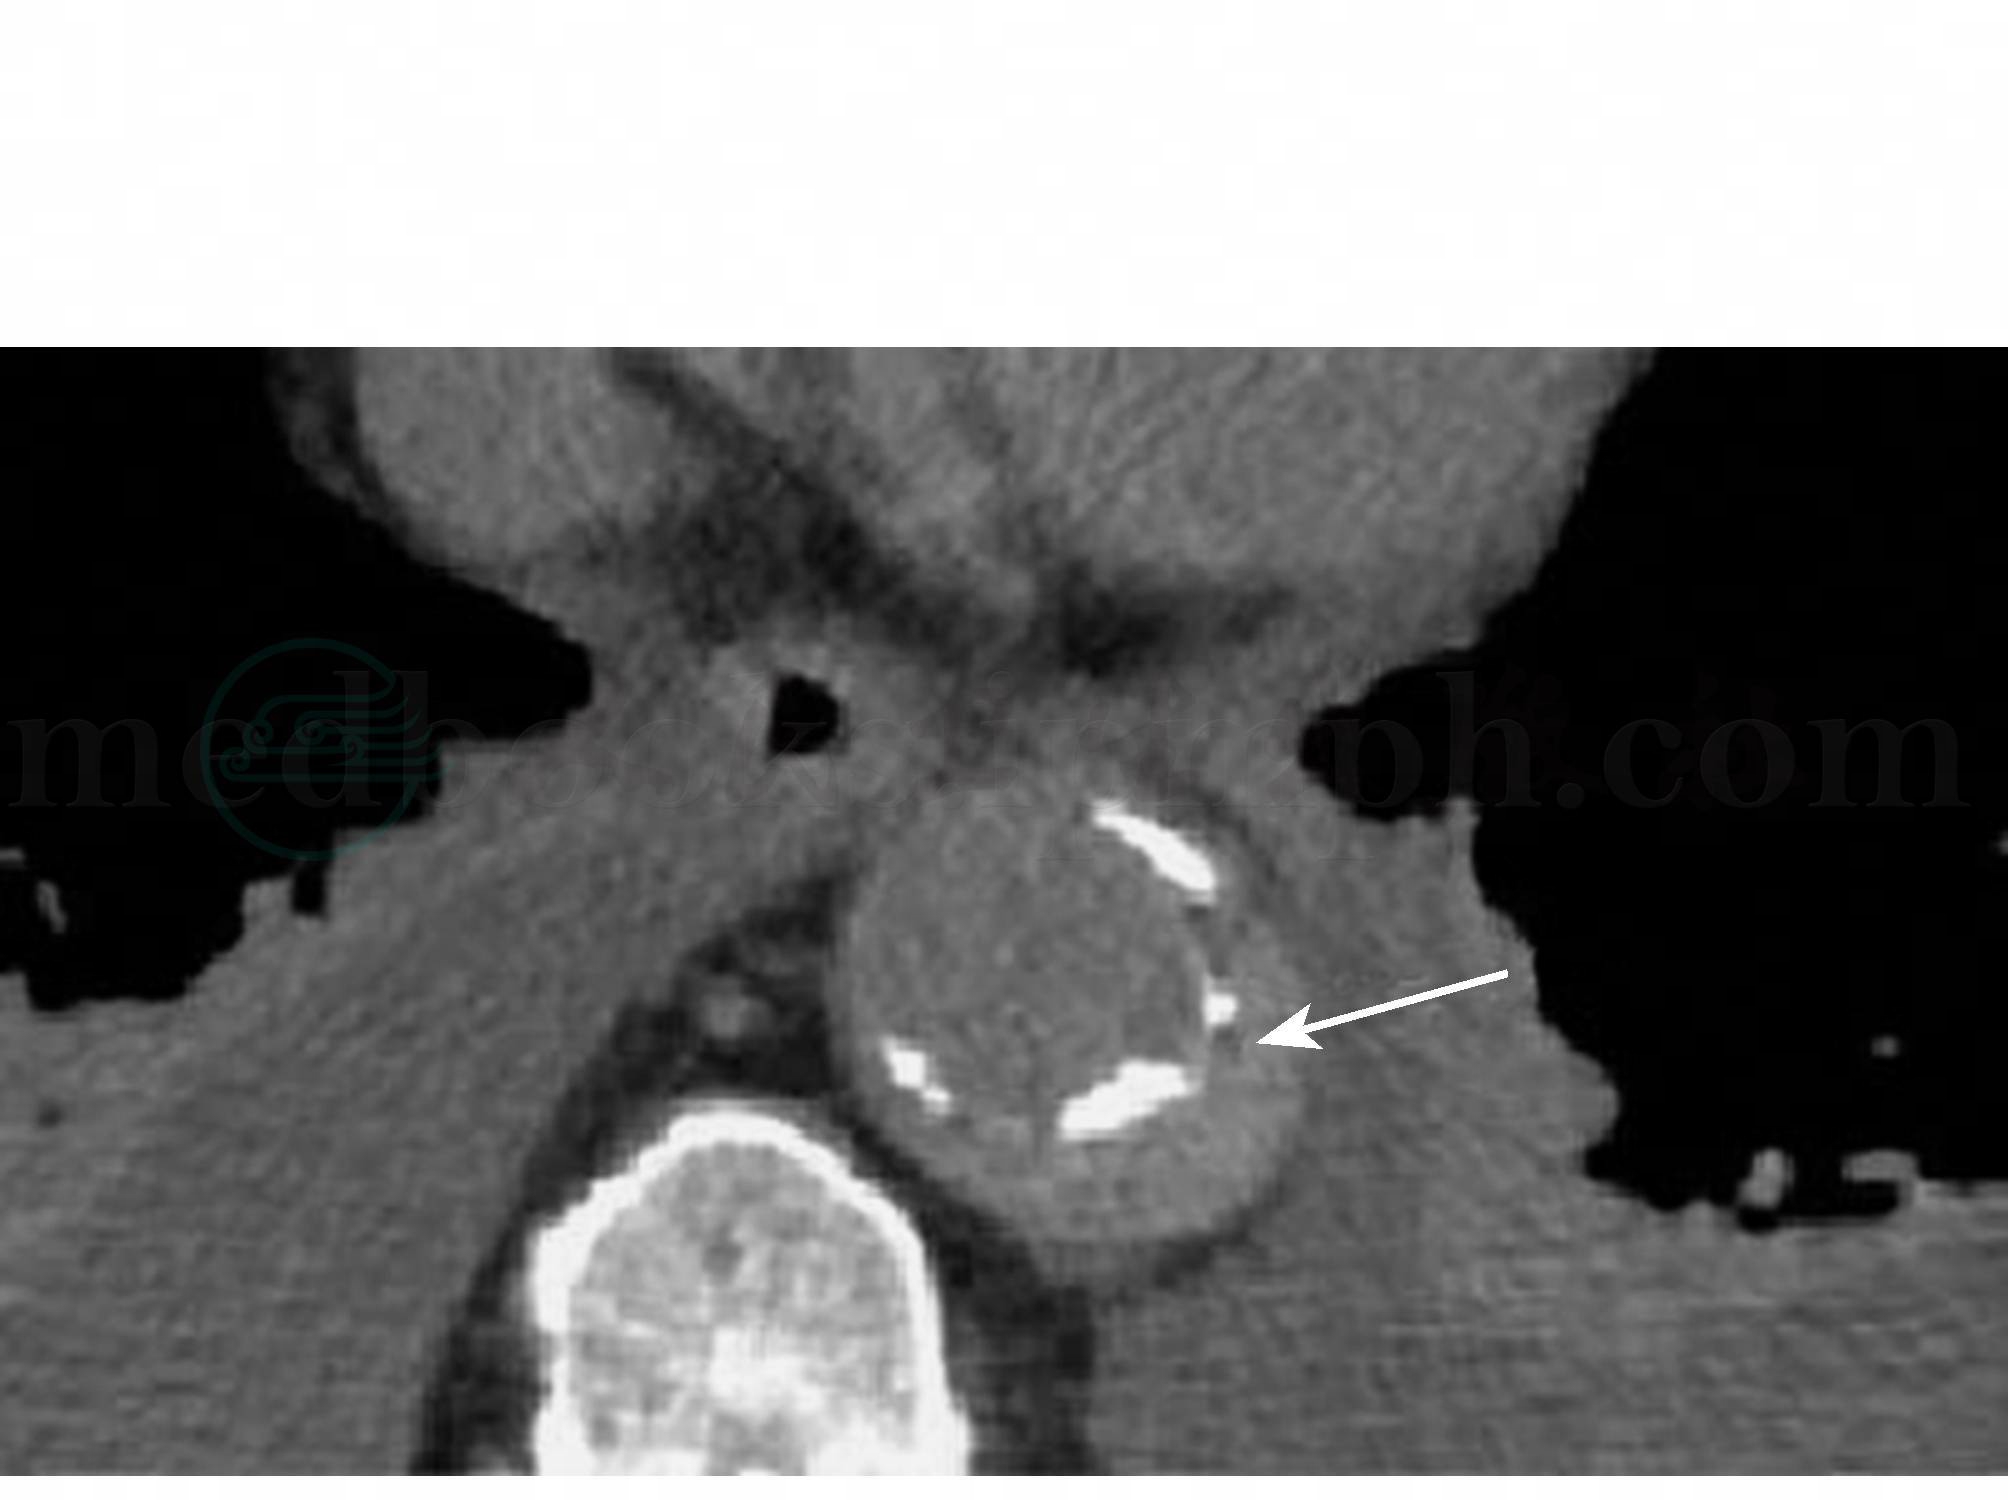

图6 主动脉壁间血肿的CT平扫所见

CT平扫示降主动脉壁增厚,并可见钙化内膜向主动脉腔内移位